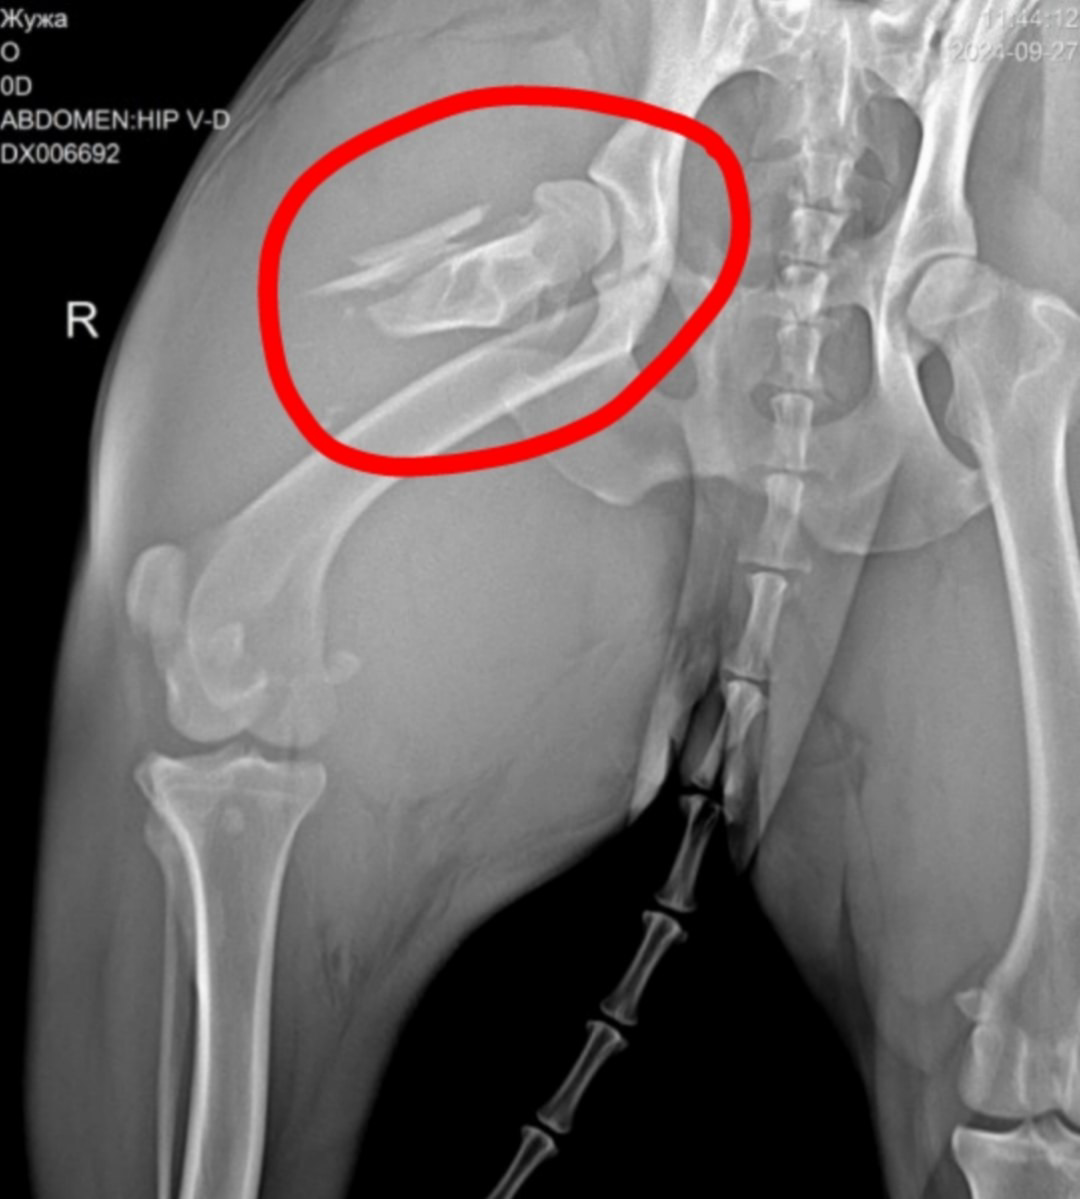

Рентгеновский снимок моего правого бедра

Сегодня были у хирурга, сложный перелом подтвердился, на снимке видно, как кость разнесло на осколки и сустав тоже повреждён.

«Прогнозы висят в воздухе.» - сказал хирург, - «будем открывать, чистить осколки и принимать решение как собирать бедро. Сколько по времени продлится операция? Сколько восстановление? Будет ли ходить? Неизвестно.»

Сейчас меня заберут у хозяев, поместят в клетку на ночь без еды, только немного воды, завтра несколько часов будут готовить к операции, потом сбреют шерсть на бедре, сделают разрез сантиметров 30, будут вычищать осколки и собирать заново тазобедренный сустав и что из этого выйдет - неизвестно. Точно будет пластина или спицы - что конкретно - решат во время операции.

Я на рентгене. Пришлось лечь на раздробленное бедро.